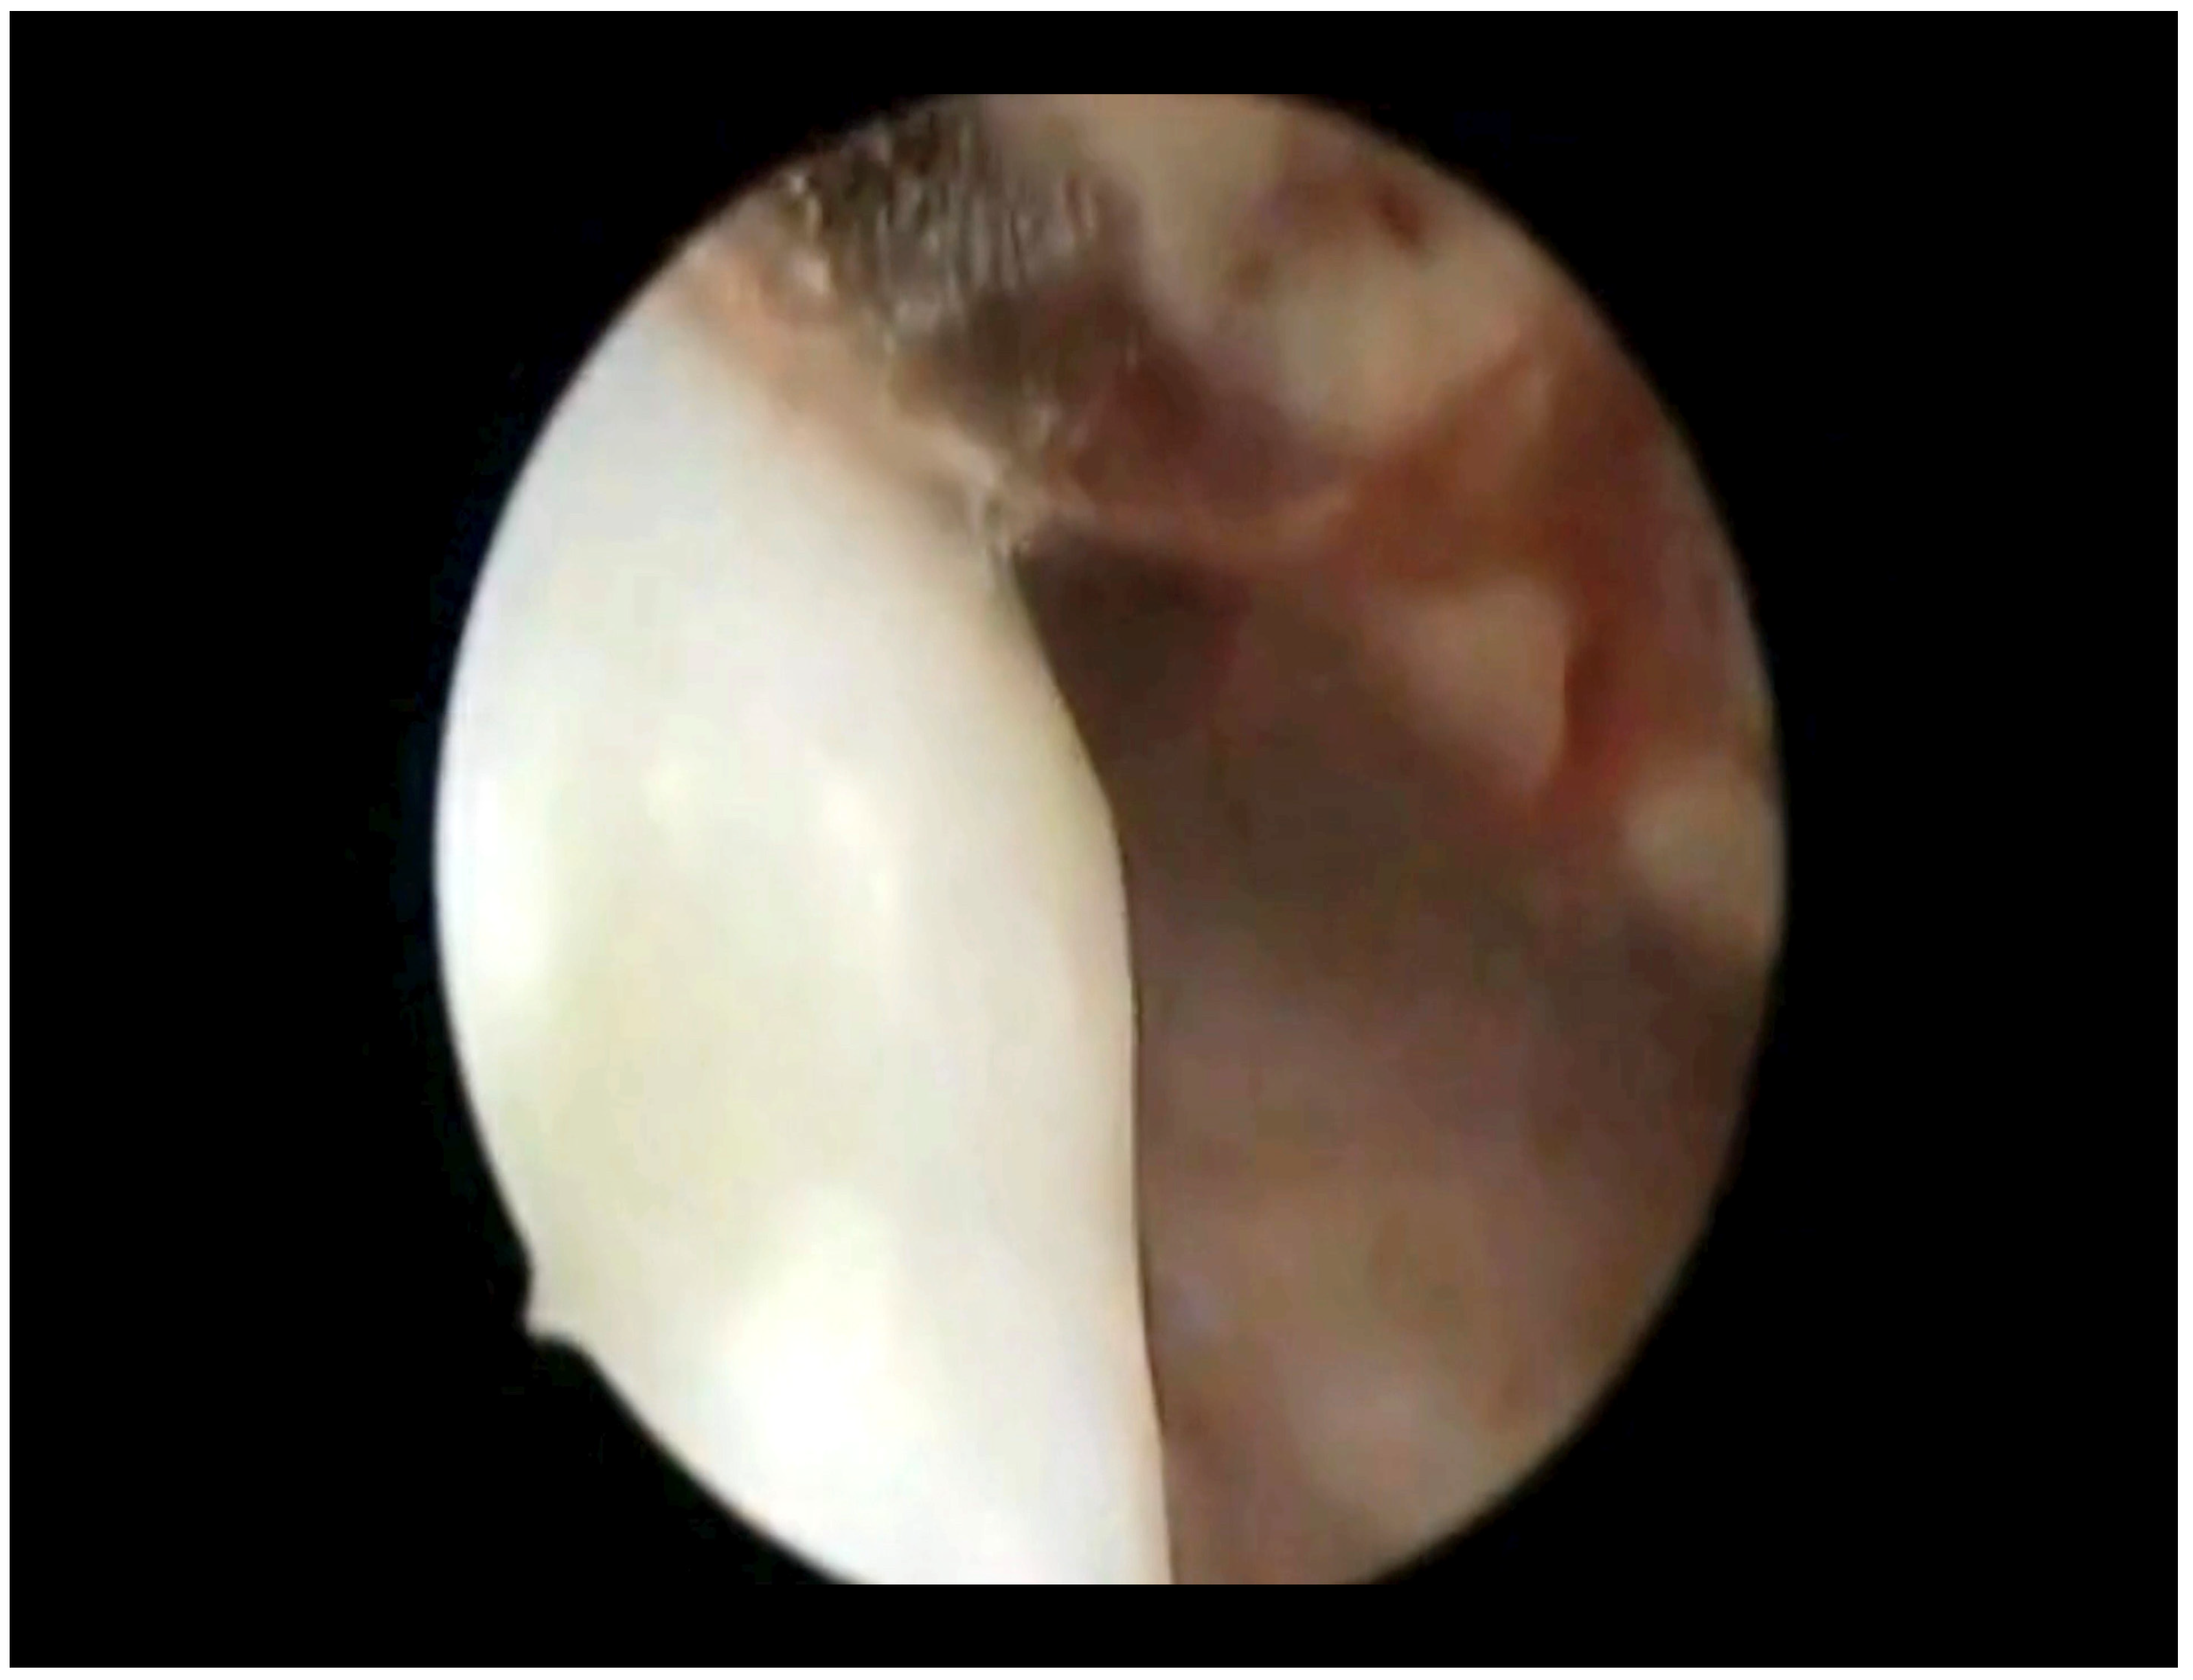

Primary Malignant Melanoma of The Endocervix Uteri and Outpatient Hysteroscopy as a Diagnostic Tool: Case Report and Literature Overview

3. Results